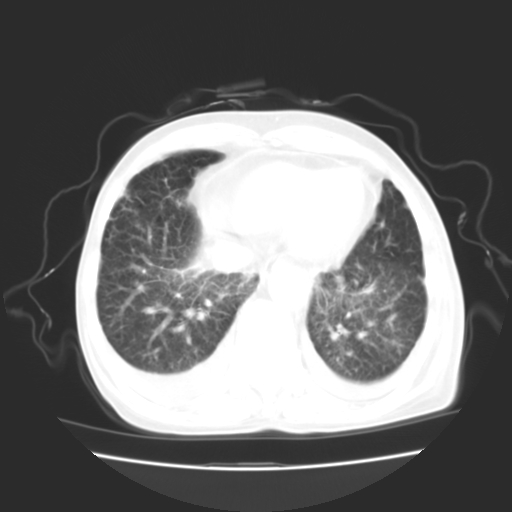

女70y乳腺ca(针吸活检)

多部位转移瘤的诊断可以肯定,我的疑问是:双肺对称高密度影及胸水是否为心衰肺水肿,病人体虚弱,不好意思图象传的乱![em9]

肺部病变为淋巴转移,肝脏转移,及局部淋巴转移。胸水可能为淋巴回流受阻(血性的考虑胸膜转移)

癌性淋巴管炎,肝脏转移,瓷胆囊

1)左侧乳腺癌并左侧腋窝及纵隔淋巴结转移,两肺淋巴道转移(癌性淋巴管炎),肝脏多发性转移。2)双侧胸腔积液。3)慢性胆囊炎。

3、双肺癌性淋巴管炎;

5、肝转移瘤;

6、瓷胆囊。

1)左侧乳腺癌并左侧腋窝及纵隔淋巴结转移,肝脏多发性转移。2)双侧胸腔积液伴双肺蝶翼样磨玻璃高密度影,双侧肺门血管影增粗(图像不全,肺门层面没纵隔窗),考虑心功能不全所致。3)慢性胆囊炎伴壁钙化。